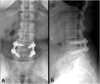

Case presentation: A 51-year-old female presented at a spine clinic with low back pain, bilateral leg pain and difficulty walking. Magnetic resonance imaging of the lumbar spine showed evidence of severe central canal stenosis due to extensive epidural lipomatosis. She was initially advised to lose weight and undergo a 3-month course of physiotherapy. However, because of lack of improvement, she was scheduled for and underwent L4-S1 posterior spinal decompression and L4-L5 posterior spinal instrumented fusion. At 12-month follow-up, the patient reported no pain and retained the ability to walk regular distances without experiencing discomfort.